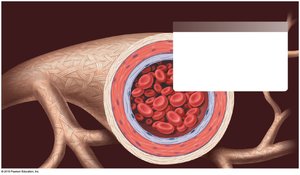

Except for capillaries, blood vessel walls consist of three layers (tunics):

Adventitia (Tunica Externa): The outermost layer, primarily connective tissue, providing structural support and protection.

Media (Tunica Media): The middle layer, composed of smooth muscle and connective tissue, responsible for vasoconstriction and vasodilation.

Intima (Tunica Intima): The innermost layer, consisting of endothelium and connective tissue, providing a smooth lining for blood flow.